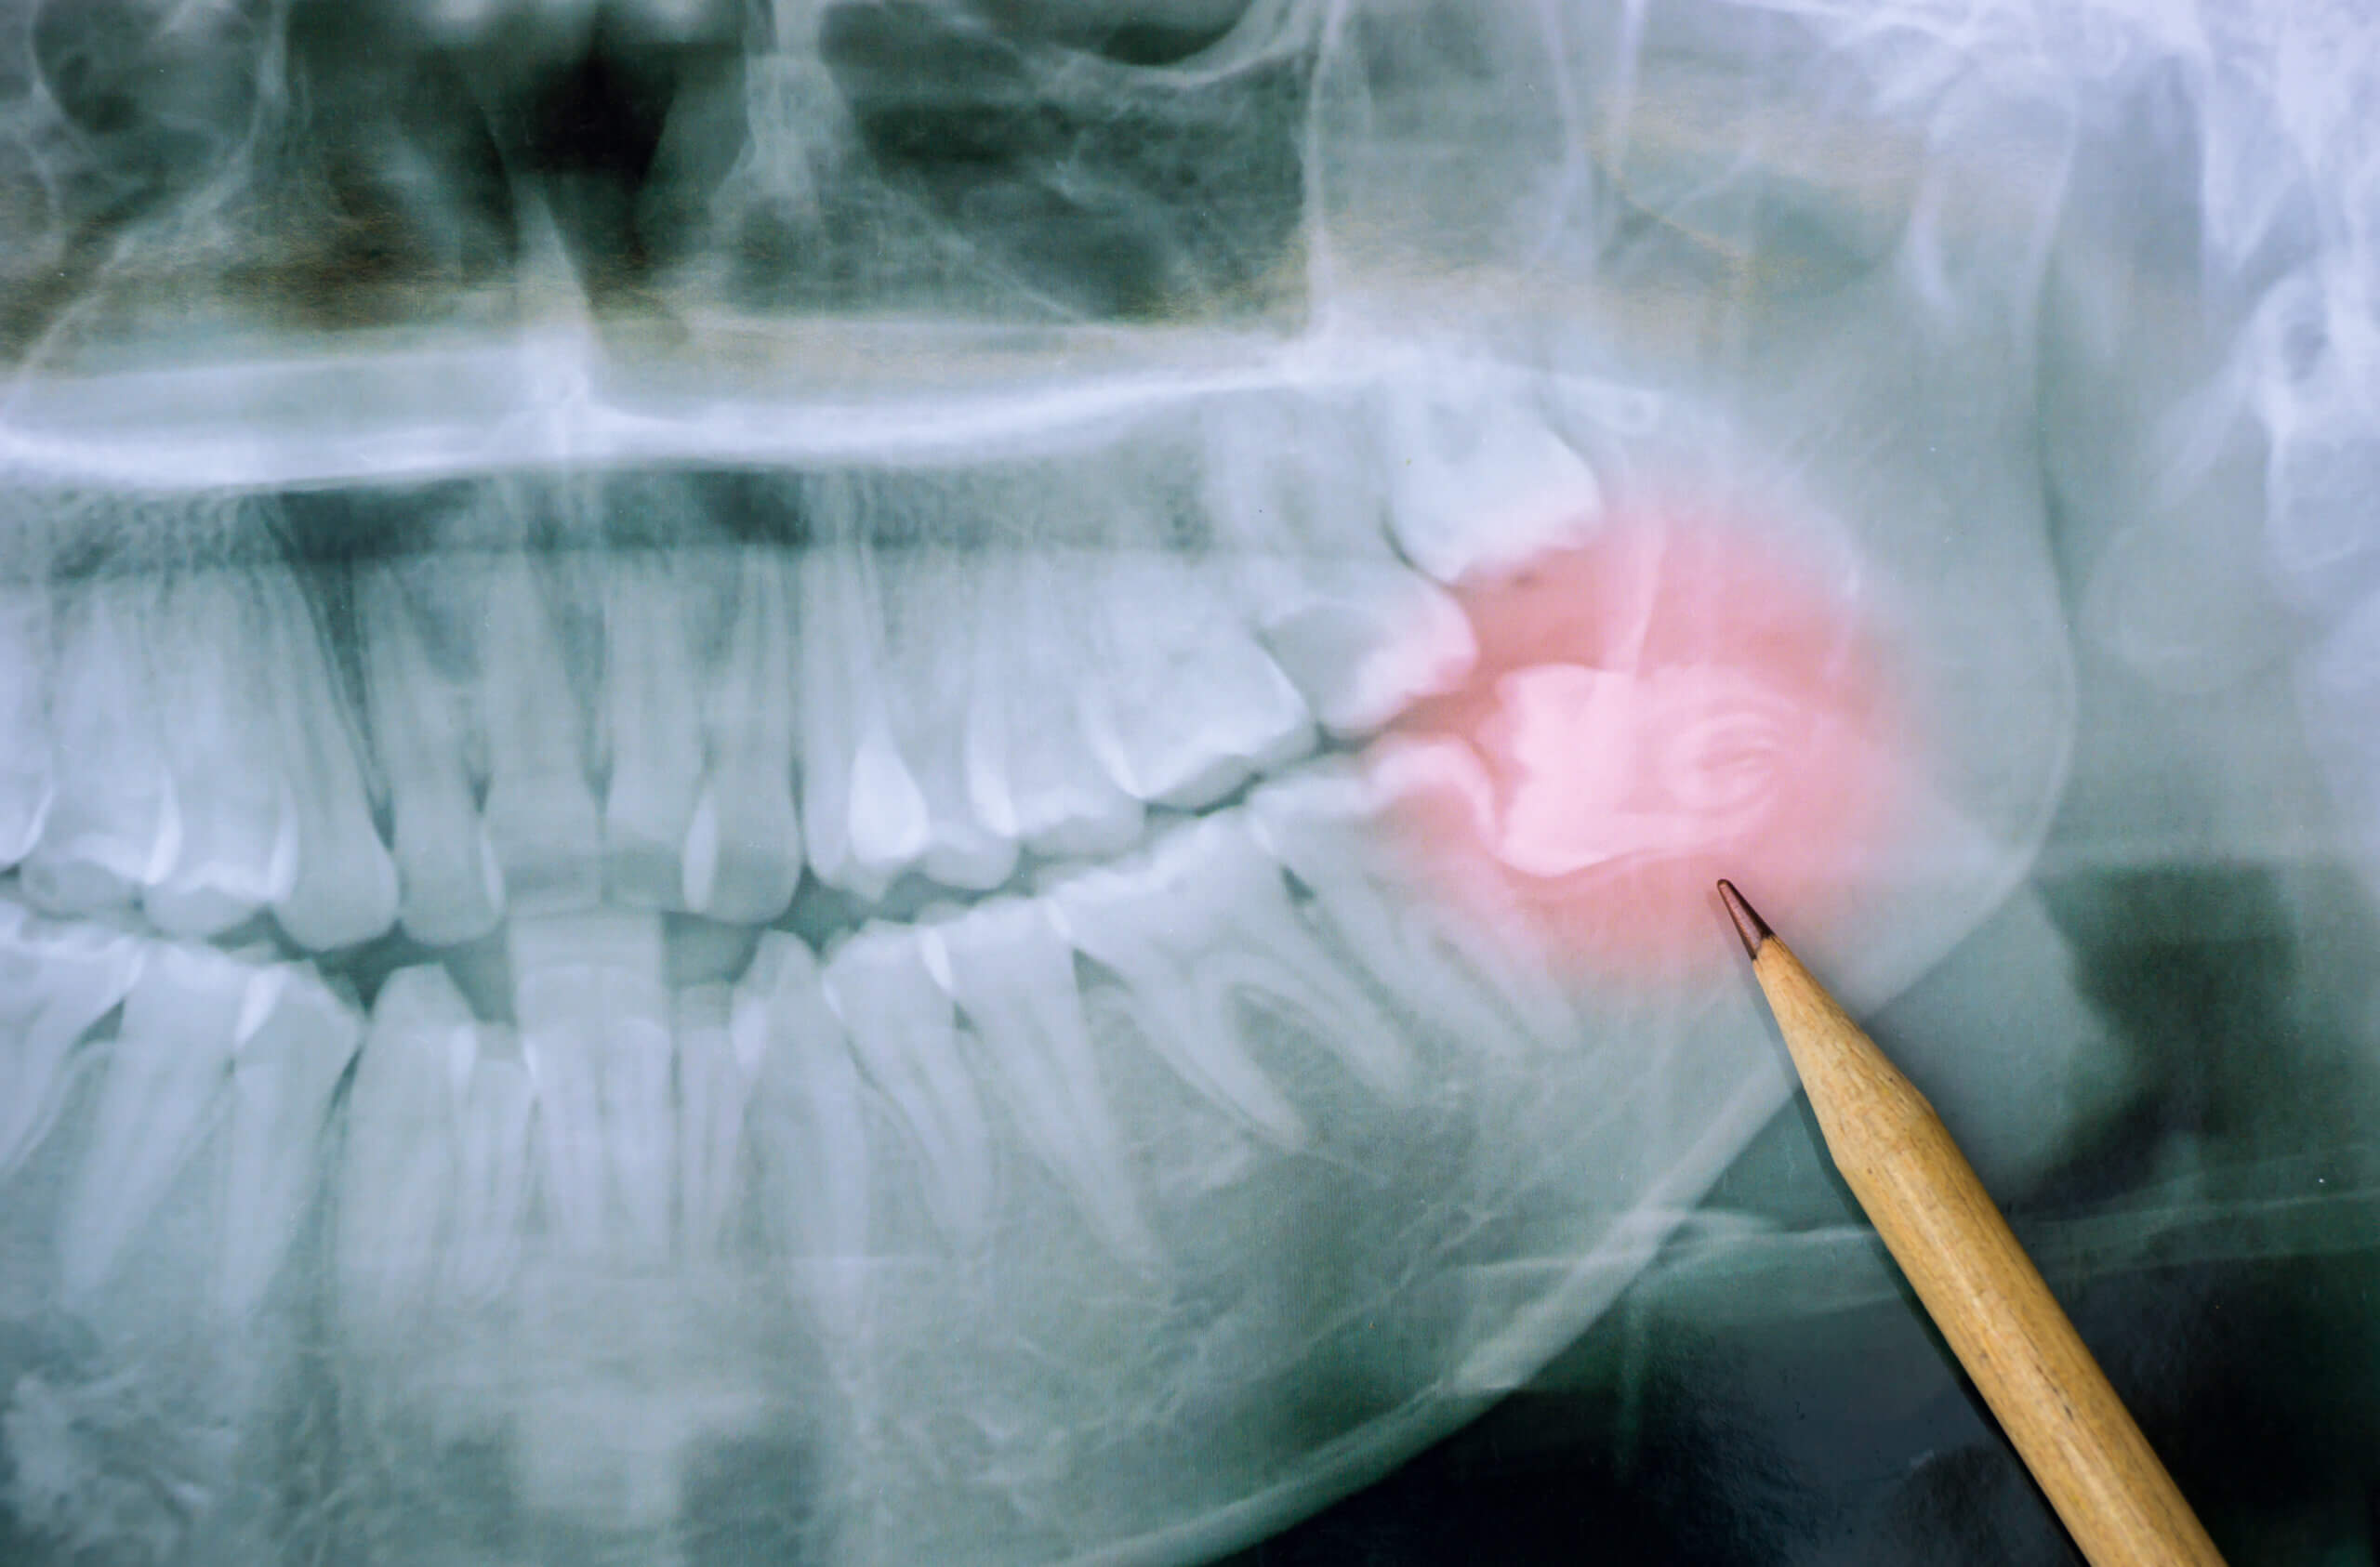

Wisdom Teeth Removal

Pain Free Wisdom Teeth Removal Sometimes wisdom teeth come in exactly as they should, upright and in exactly the right position. Unfortunately, that is the exception and not the rule. [...]